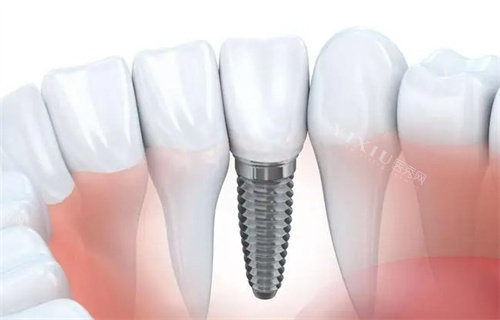

材料特性:选用符合行业标准的医用材料,这些材料与人体组织的相容性较好,降低了不良反应发生的可能性。

初期固定结果:通过对螺纹结构和表面特性的优化设计,部分型号的种植体在植入后能够获得较好的初期固定结果,这对后续的愈合过程有积极作用。